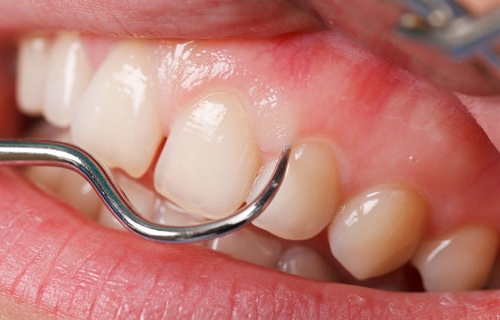

Parodontitin əsas əlamətləri bunlardır:

- Diş ətində şişkinlik və qızartı

- Diş ətində qanamağa meyllilik